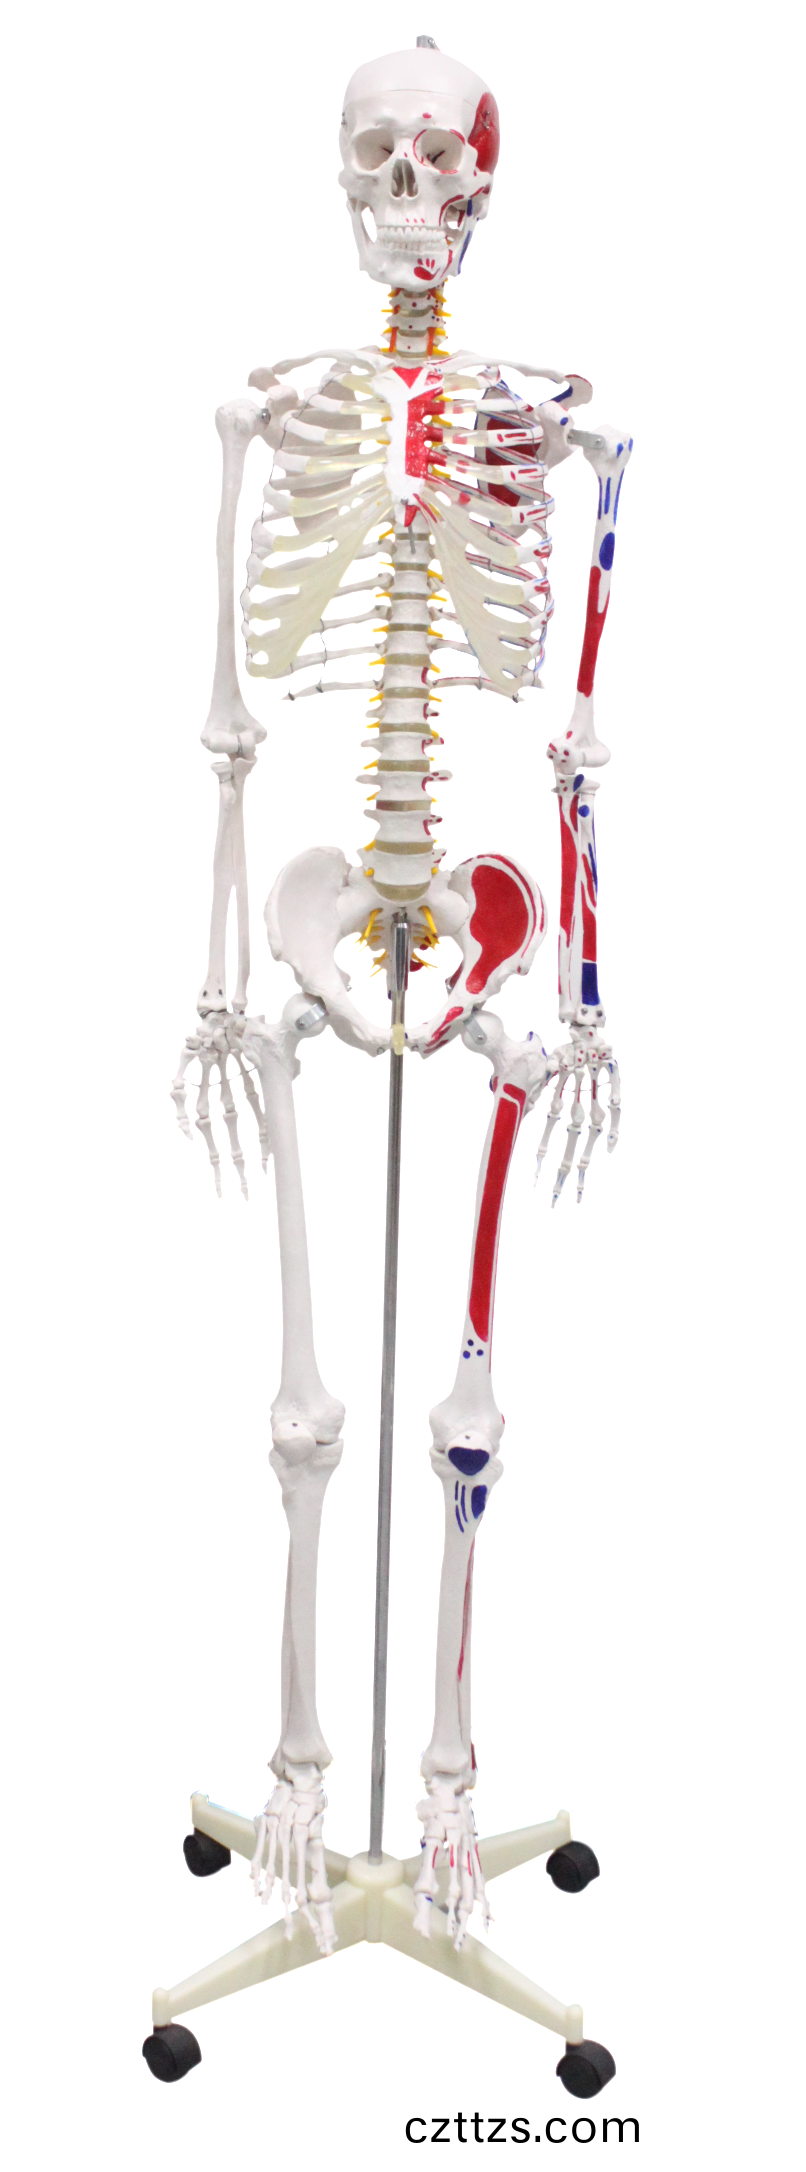

人體骨骼半邊肌肉着色糢型

産品編號:HAM0159

功能特點:●真實尺寸大小●由顱骨、軀榦骨咊上肢骨、下......